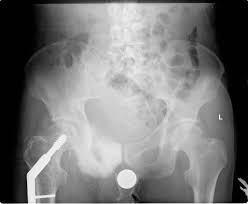

What Are The Symptoms Of Pelvic Bone Cancer : Surgical Management Of Pelvic Primary Bone Tumors Involving The Sacroiliac Joint Sciencedirect - Bone cancer destroys normal bone tissue.. More rarely, the base of the skull is affected. Chondrosarcoma is a cancer that can begin in the bones or tissue near bones, often in the hip, pelvis, and shoulder. Symptoms if cancer has spread to the lymph nodes lymph nodes are part of a system of tubes and glands in the body that filters body fluids and fights infection. The most common locations for chondrosarcoma tumors are in the pelvis, hip and shoulder. Rarely, people with a bone sarcoma may have symptoms such as fever, generally feeling unwell, weight loss, and anemia, which is a low level of red blood cells.

A high temperature (fever) of 38c (100.4f) or above It can spread to distant organs, such as the lungs. Bone cancer is rare, making up less than 1 percent of all cancers. Pelvic bone neoplasms are seldom immediately diagnosed and, therefore, may result in significant morbidity and mortality. Osteosarcoma is probably the most common disease that is related to pelvic bone cancer, with chondrosarcoma following close behind it. Hip pain is a common complaint like that of knee or back pain. At first, the pain is not constant. Bone metastases can weaken your bones and lead to symptoms like bone pain. The bones are the most common place where metastatic breast cancer cells tend to go. Chondrosarcoma is a cancer that can begin in the bones or tissue near bones, often in the hip, pelvis, and shoulder. Symptoms of testicular cancer may include: Can bone cancer be found early? Having too much calcium in your blood , which has numerous causes, is a dangerous condition called.

Bone cancer can begin in any bone in the body, but it most commonly affects the pelvis or the long bones in the arms and legs. There are many pelvic cancer symptoms a person can experience. Bone cancer develops in the skeletal system and destroys tissue. The symptoms of bone cancer are: In contrast, some other metastatic tumors, such as those from the prostate, are commonly osteoblastic, meaning that they form new bone and increase the brittleness of the bones. Rarely, people with a bone sarcoma may have symptoms such as fever, generally feeling unwell, weight loss, and anemia, which is a low level of red blood cells. Although breast cancer can spread to any bone, the most common sites are the ribs, spine, pelvis, and long bones in the arms and legs. Osteosarcoma is probably the most common disease that is related to pelvic bone cancer, with chondrosarcoma following close behind it. A primary bone cancer is one that starts from bone. Although less often, other areas (such as the ribs) may be affected. Can bone cancer be found early? Hip pain is a common complaint like that of knee or back pain. Get the latest health information from mayo clinic delivered to your inbox.

What Is Pelvic Bone Cancer With Pictures from images.infobloom.com Pelvic bone neoplasms are seldom immediately diagnosed and, therefore, may result in significant morbidity and mortality. Rarely, people with a bone sarcoma may have symptoms such as fever, generally feeling unwell, weight loss, and anemia, which is a low level of red blood cells. When cancer spreads to your bones, it can cause pain and make them weak enough to fracture. If you are concerned about any changes you experience, please talk with your doctor. It can spread to distant organs, such as the lungs. Signs of anemia are tiredness, weakness, and shortness of breath. Bone metastasis may be the first sign that you have cancer, or bone. Bone cancer destroys normal bone tissue.

The bones are the most common place where metastatic breast cancer cells tend to go. A person may, for example, have lumps in the pelvic region or experience pain in the area. Learn more about the symptoms, risk factors, diagnosis, types, treatment, and outlook for bone cancer. Your red blood cell levels may drop, causing anemia. Pain, fever, and fatigue are all symptoms associated with pelvic bone cancer. Chondrosarcoma is a rare type of cancer that usually begins in the bones, but can sometimes occur in the soft tissue near bones. There's no cure for metastatic bone cancer, but treatment options may help alleviate symptoms to keep you comfortable. Pain and swelling in the. At first, the pain is not constant. Metastatic tumors of the bones are usually osteolytic, which means that they dissolve the bone and cause multiple fractures. Abstract low back pain and sciatica are usually attributed to localized structural pathology; The long bones of the body — such as the arms and legs — and the pelvis are commonly affected. Symptoms if cancer has spread to the lymph nodes lymph nodes are part of a system of tubes and glands in the body that filters body fluids and fights infection.